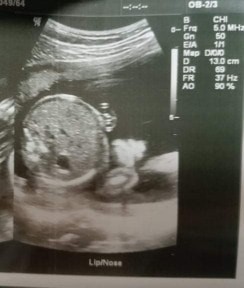

หัวน้องนำแล้วแต่ไม่ลงเชิงกราน 37+4 w แล้วค่ะ

ขอถามแม่ๆที่มีประสบการณ์หน่อยค่ะใครทราบบ้าง กรณีแบบเรา น้องเอาหัวนำล่าง แต่ไม่ลงเชิงกราน ท่าเดิมมา 3 นัดแล้วค่ะ นอนแบบ 08:10 นาฬิกา ไม่เชิงขวางค่ะ แต่เหมือนจะลงก็ไม่ลงมากกว่า ตะแคงๆ ตอนนี้ 37+4 เลยอยากทราบว่า อายุครรภ์แบบนี้แล้วน้องยังไม่อยู่ในท่าพร้อมคลอด ส่วนใหญ่จะได้คลอดเองหรือผ่าหรอคะ ขอบคุณค่ะ 😂🙏#ขอคำแนะนำหน่อยค่ะ #ขอบคุณสำหรับคำตอบค่ะ #ท้องแรกคะ #ใครมีประสบการณ์